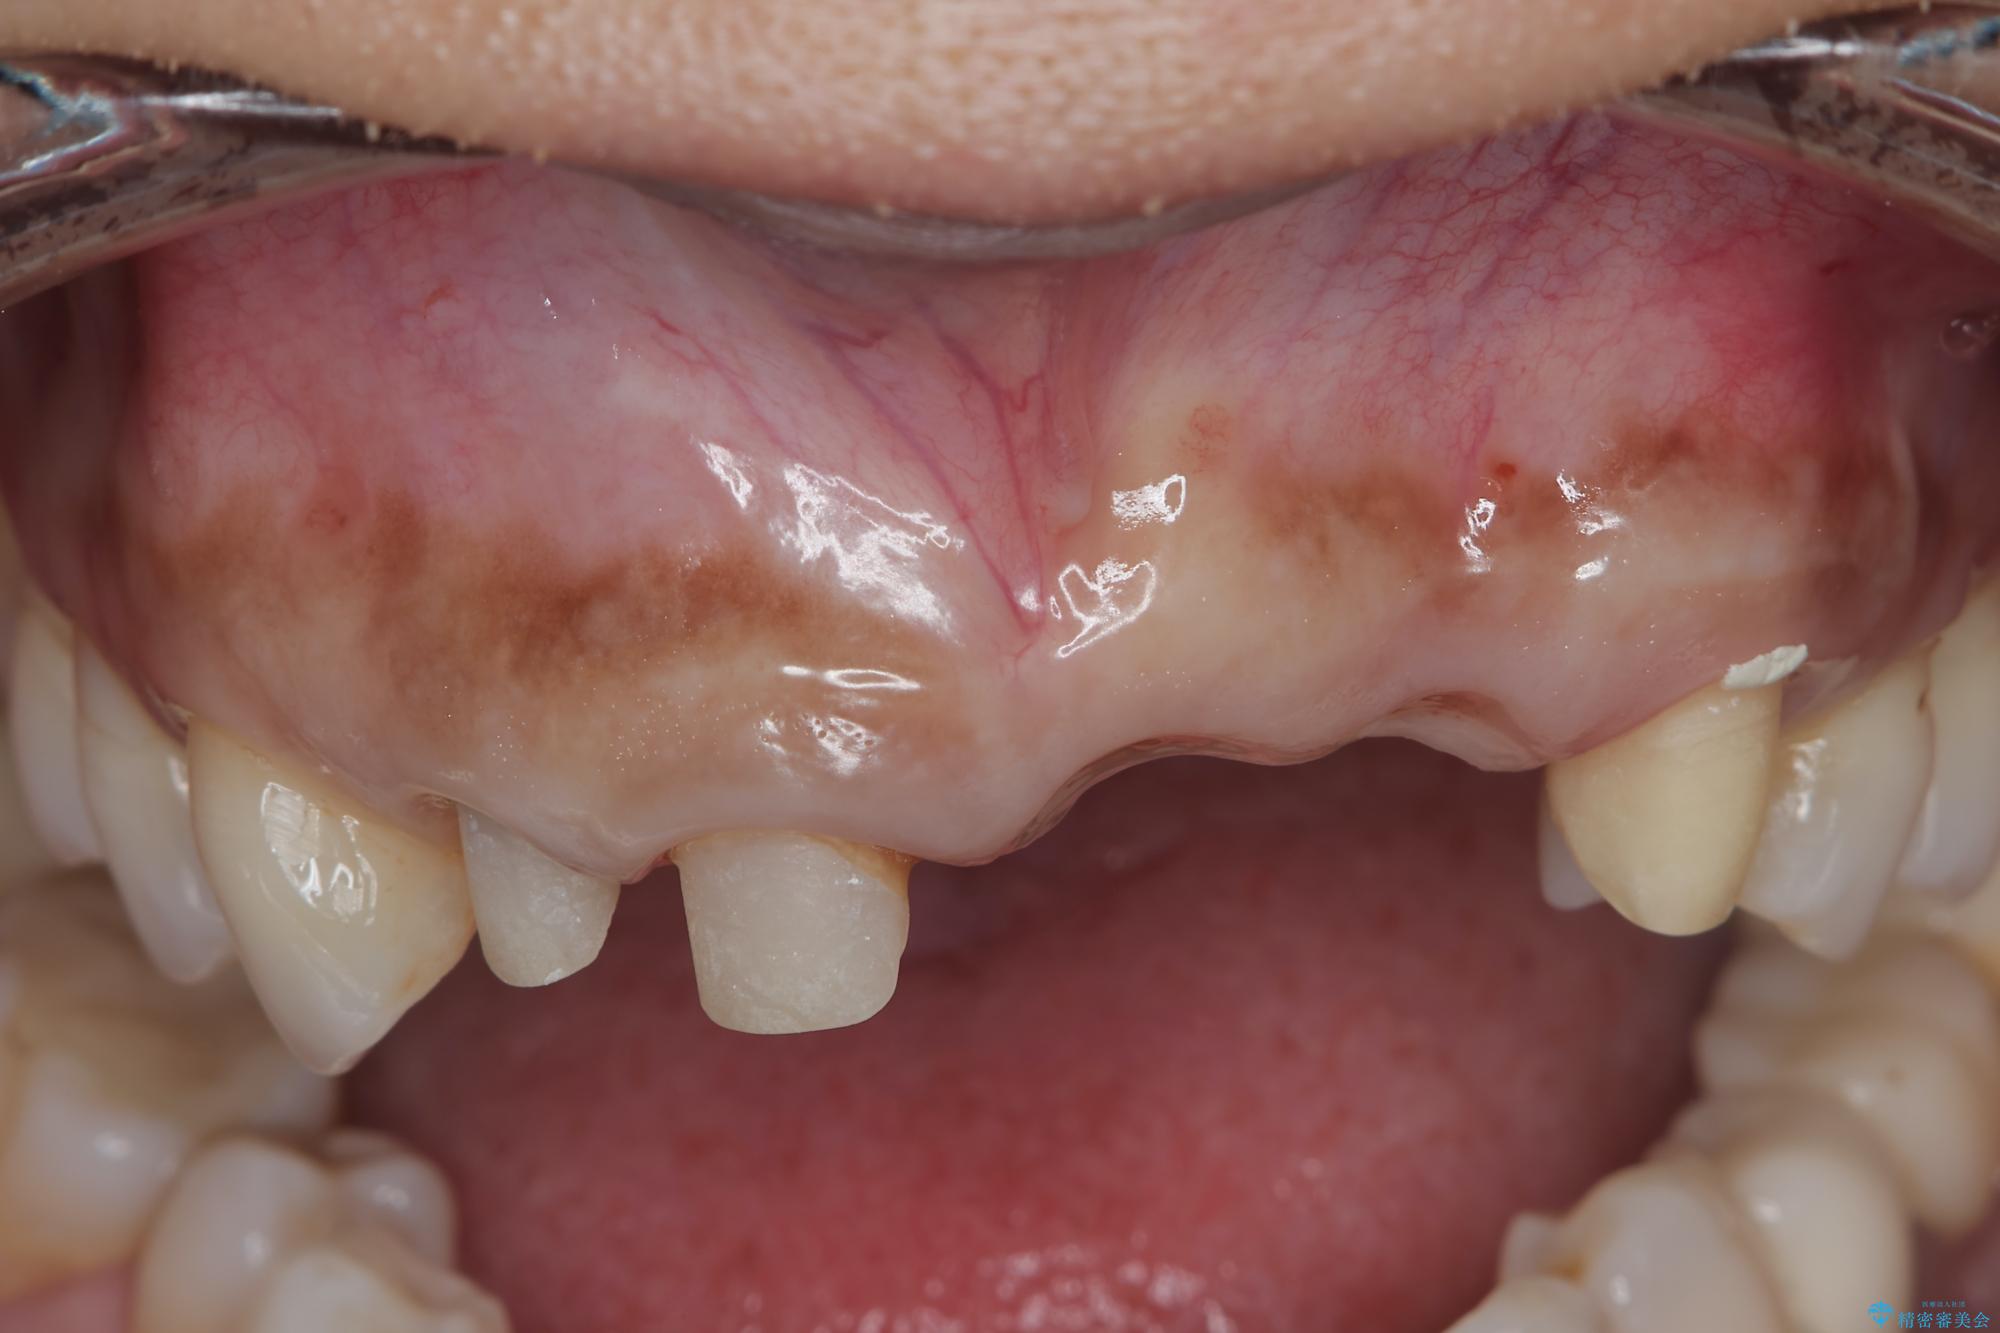

来院主訴

前歯がグラグラし、においもする、とのことで改善を求めて来院されました。

治療前

歯槽堤保存術を併用したブリッジ治療 治療前画像 歯槽堤保存術を併用したブリッジ治療 治療前画像 歯槽堤保存術を併用したブリッジ治療 治療前画像 歯槽堤保存術を併用したブリッジ治療 治療前画像 歯槽堤保存術を併用したブリッジ治療 治療前画像 歯槽堤保存術を併用したブリッジ治療 治療前画像 歯槽堤保存術を併用したブリッジ治療 治療前画像 歯槽堤保存術を併用したブリッジ治療 治療前画像 歯槽堤保存術を併用したブリッジ治療 治療前画像 歯槽堤保存術を併用したブリッジ治療 治療前画像